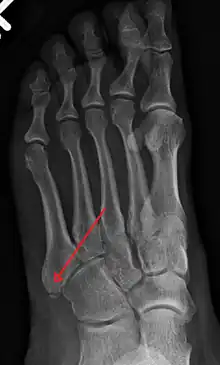

Fracture of the base of the 5th metatarsal

The metatarsal bones are often broken by association football (soccer) players. These and other recent cases have been attributed to the lightweight design of modern football boots, which provide less protection to the foot. In 2010 some football players began testing a new sock that incorporated a rubber silicone pad over the foot to provide protection to the top of the foot.[8] Stress fractures are thought to account for 16% of injuries related to sports participation, and the metatarsals are the bones most often involved. These fractures are sometimes called march fractures, based on their traditional association with military recruits after long marches. The second and third metatarsals are fixed while walking, thus these metatarsals are common sites of injury. The fifth metatarsal may be fractured if the foot is oversupinated during locomotion.[9]